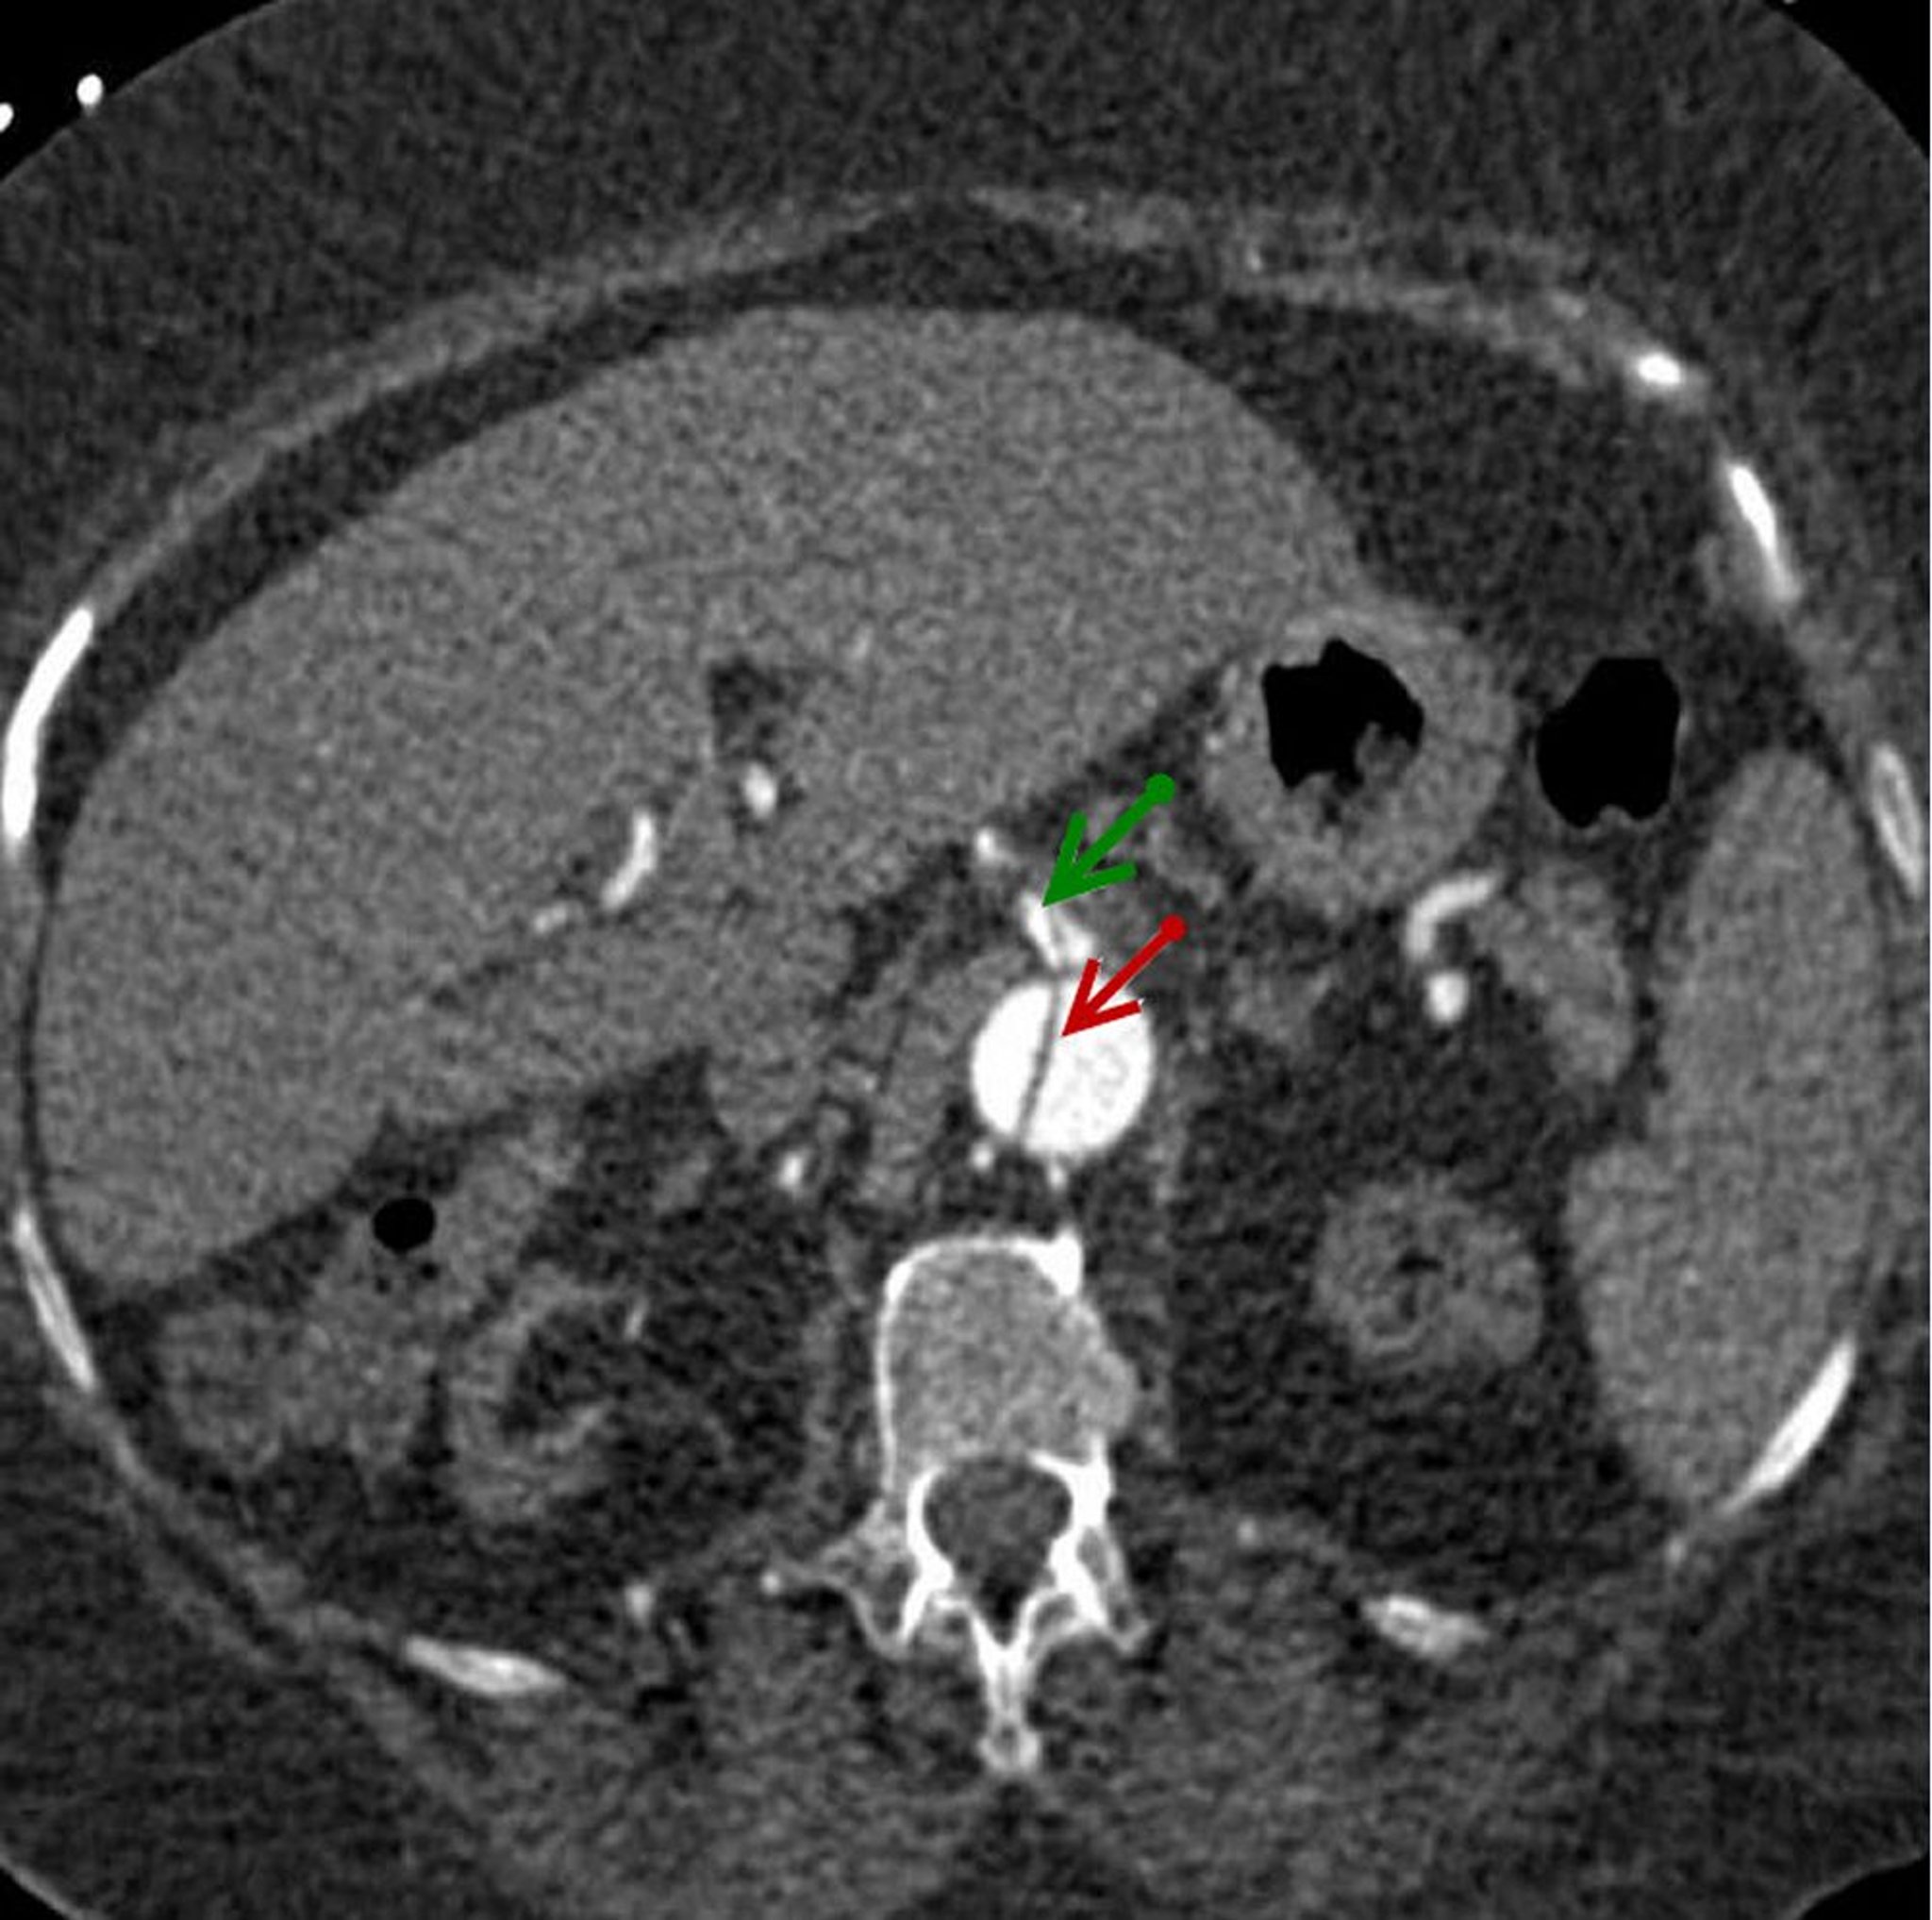

Dissection aortique abdominale

Image axiale du lambeau de dissection dans l'aorte abdominale descendante (flèche rouge) qui s'étend dans l'artère mésentérique supérieure (flèche verte).